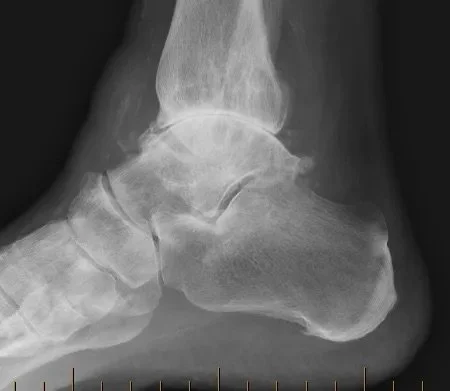

Weight-bearing X-rays are the primary imaging study used to confirm the diagnosis and may demonstrate joint space narrowing, bone spurs, deformity, or evidence of prior trauma. In more complex cases, CT scans or MRI may be obtained to further evaluate joint surfaces, alignment, or associated soft-tissue pathology.